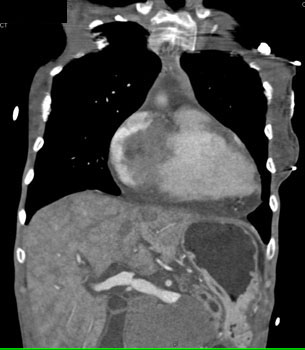

![]() | Question 14: HIV patient with increasing chest discomfort. The study was requested to rule out a pulmonary embolism. What is the diagnosis? |